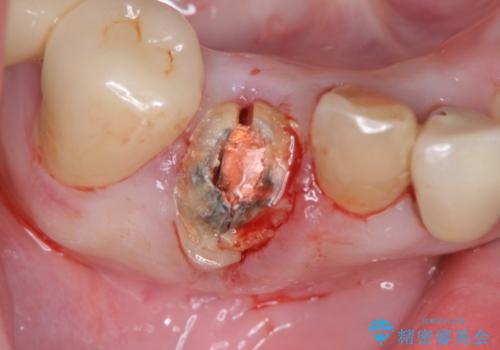

- 歯ぐきの黒っぽさ、暗い色調の前歯の改善を求めて来院されました。

金属を用いたコア・クラウンが装着されており、全ての金属を除去したのちのメタルフリー治療を計画します。

ファイバーコア・セラミッククラウンは金属を用いない審美的な治療法です。